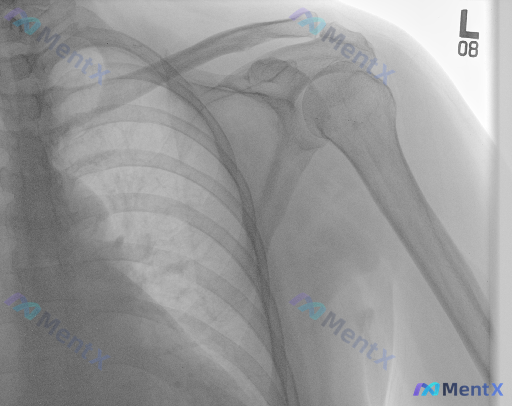

整理了一份有意思的影像讨论资料: 左侧肩部正位X光,常规读片结果是: - 肱骨近端、肩胛骨、锁骨远端未见明确骨折线 - 盂肱关节对位良好,无脱位 - 骨密度、关节间隙、肩峰形态大致正常 - 大结节上方未见明确钙化影,软组织轮廓尚可 但设定明确提示——「存在异常」。 这种「X光报“未见明显异常”但实际...